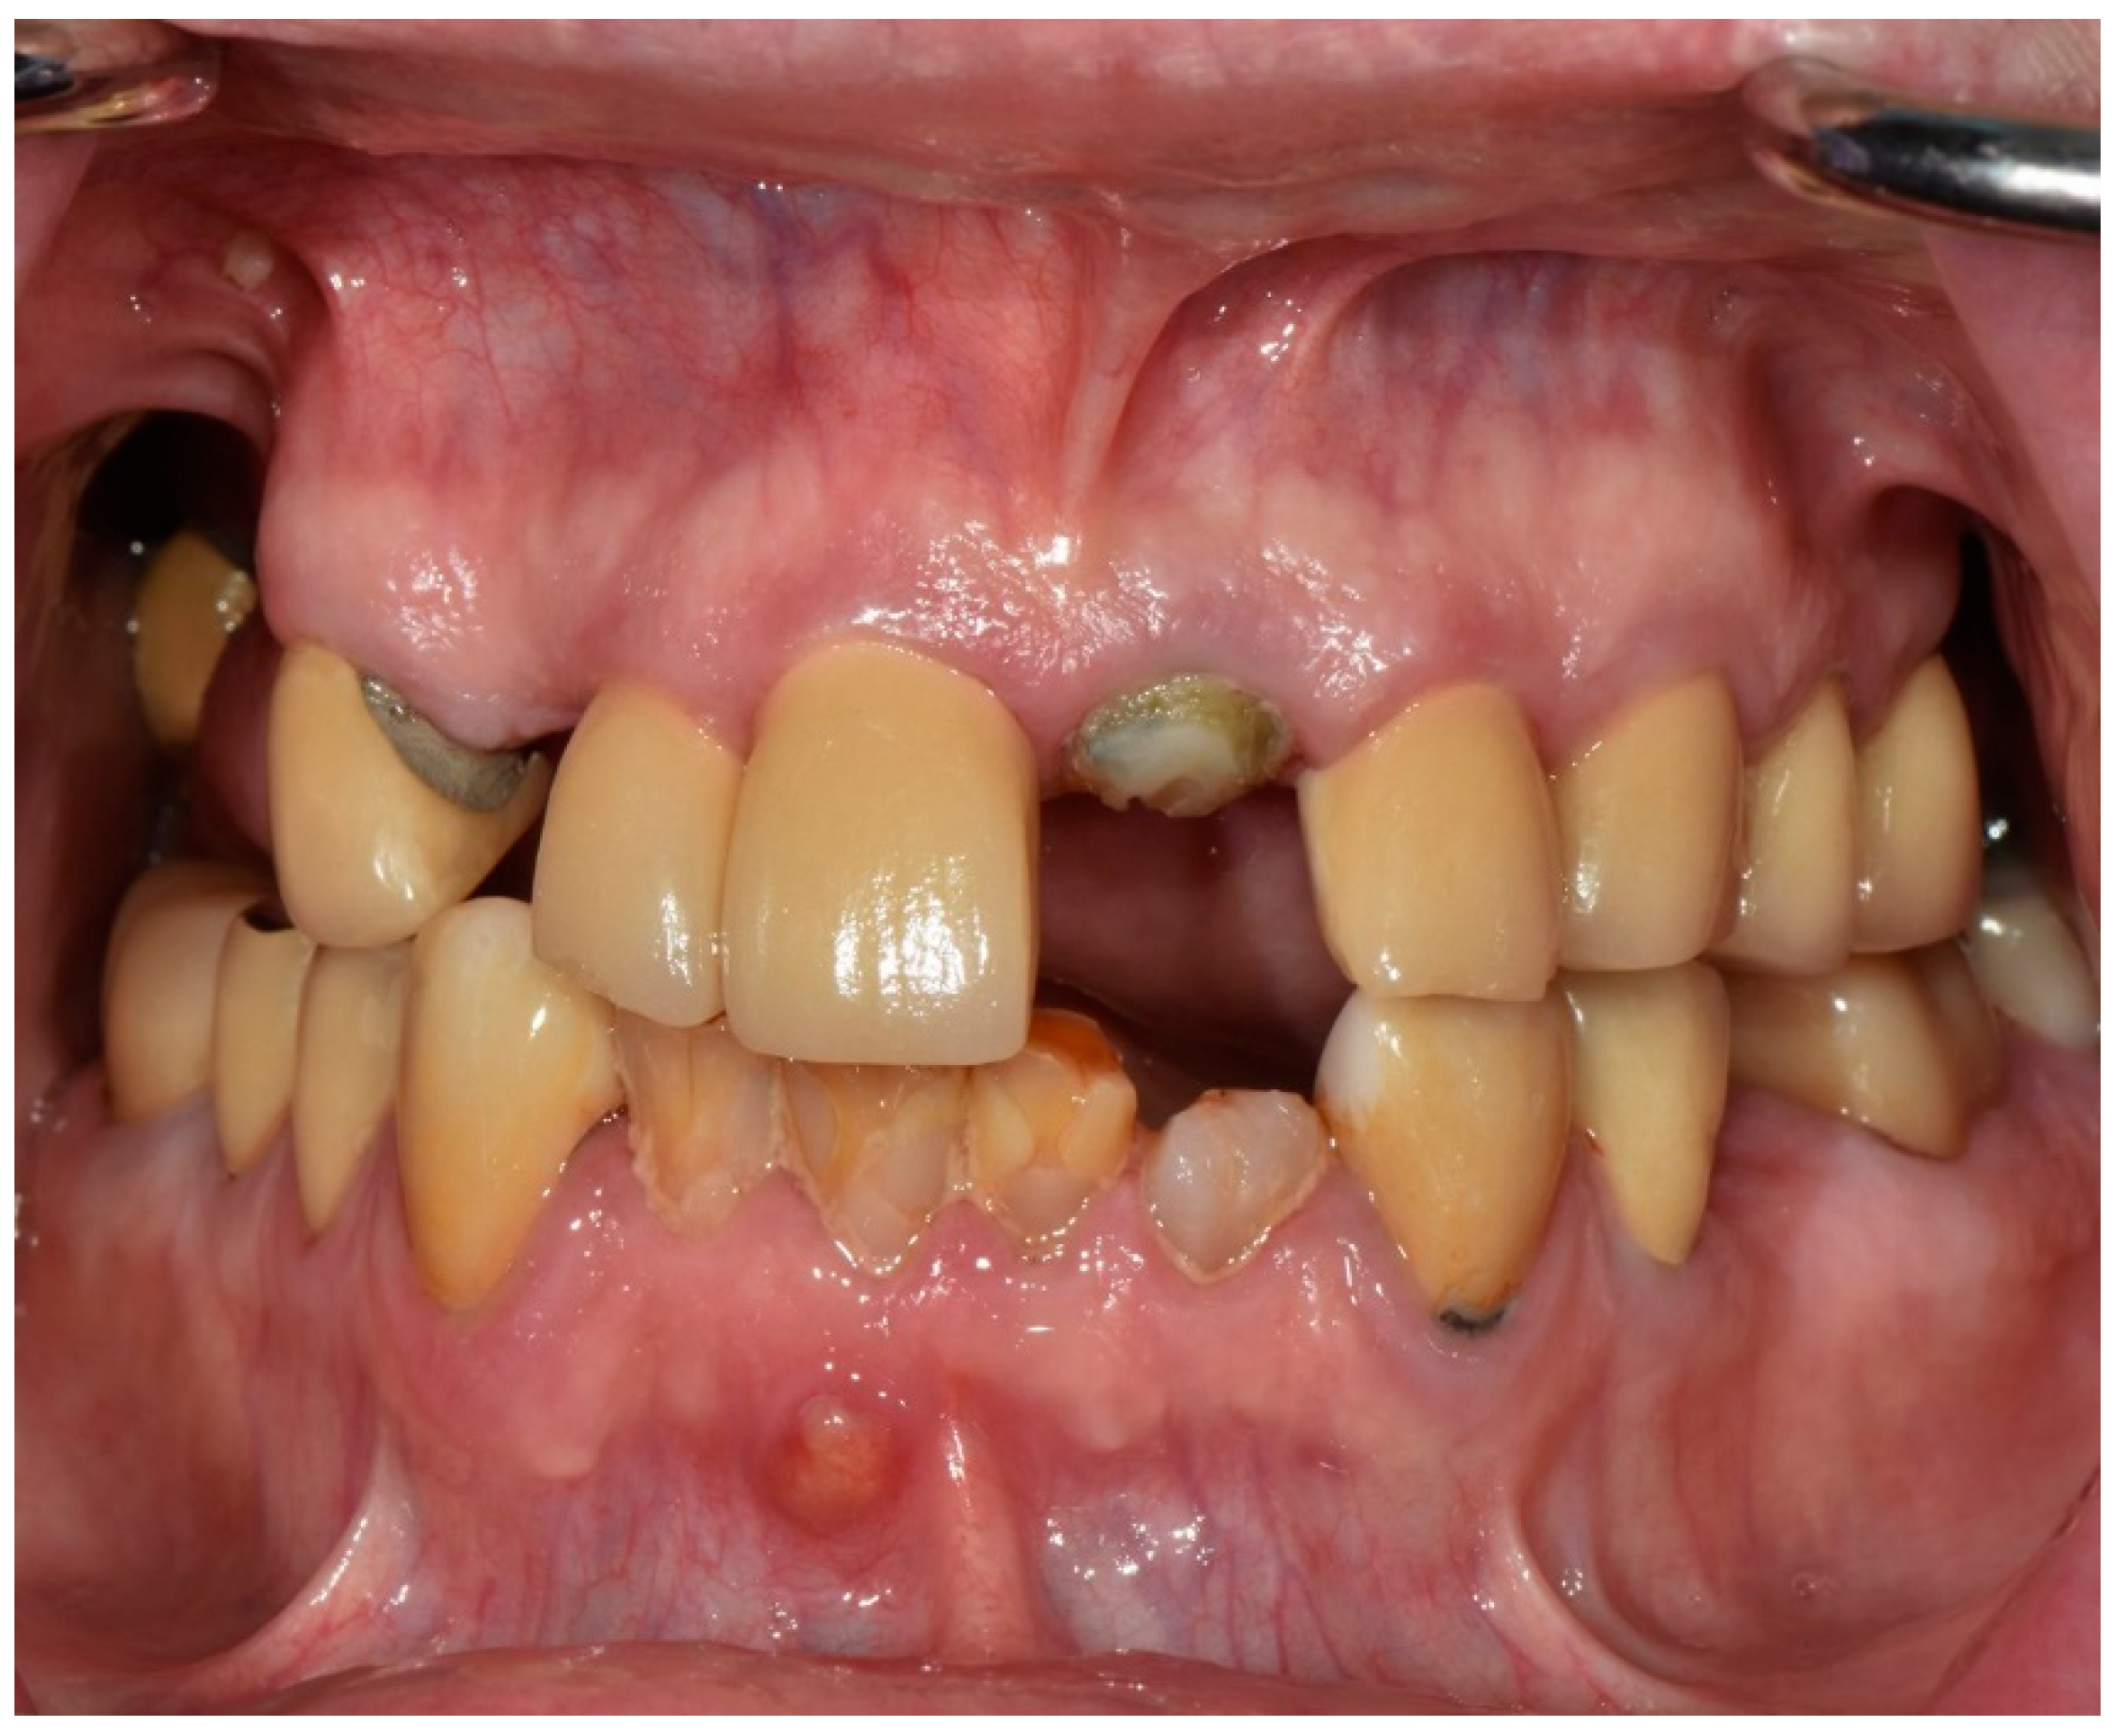

Full-Mouth Rehabilitation of a Patient with Sjogren’s Syndrome with Maxillary Titanium-Zirconia and Mandibular Monolithic Zirconia Implant Prostheses Fabricated with CAD/CAM Technology: A Clinical Report

2. Materials and Methods